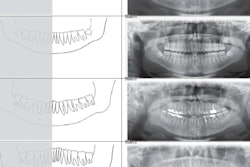

- Scan the patient using an intraoral scanner and generate an STL file. Obtain a CBCT scan and save the data as a DICOM file. Then, import both files into a design software program and superimpose them using the swab markers as guides.

- Use the surgical guide to place the implant, and install the interim prosthesis intraorally. If medically necessary, postoperative CBCT images can be used to compare the postoperative and preoperative virtual implant positions.